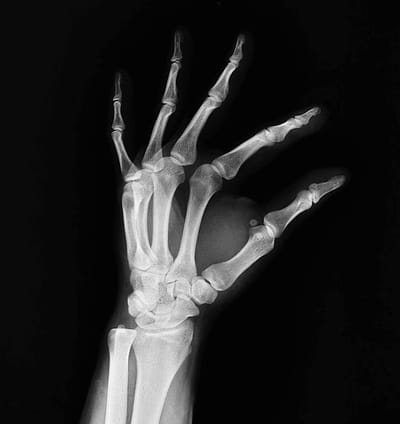

Experience the future of image segmentation with our user-friendly tool designed by radiologists, for radiologists. Experience effortless workflows and improved accuracy with our radiology and gaming-inspired controls.

We provide segmentation services for CT or MRI datasets. Our radiologist-validated results use modern AI models to produce precise annotations in the form of masks, volumes, or 3D models/meshes in any file format. This service is available for a fee.